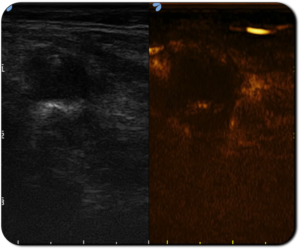

Immagine CEUS post trattamento che evidenzia l’area ipoecogena della zona di coagulazione

Paziente con linfonodo metastatico del collo da carcinoma tiroideo papillare è stato sottoposto a trattamento di Termoablazione EchoLaser con due fibre.

Immagine CEUS che evidenzia l’elevato assorbimento del contrasto del linfonodo patologico

Immagine CEUS che mostra la completa assenza di enhancement dopo il trattamento

Immagini per gentile concessione del Dott. Mauri (Ospedale IEO, Milano)